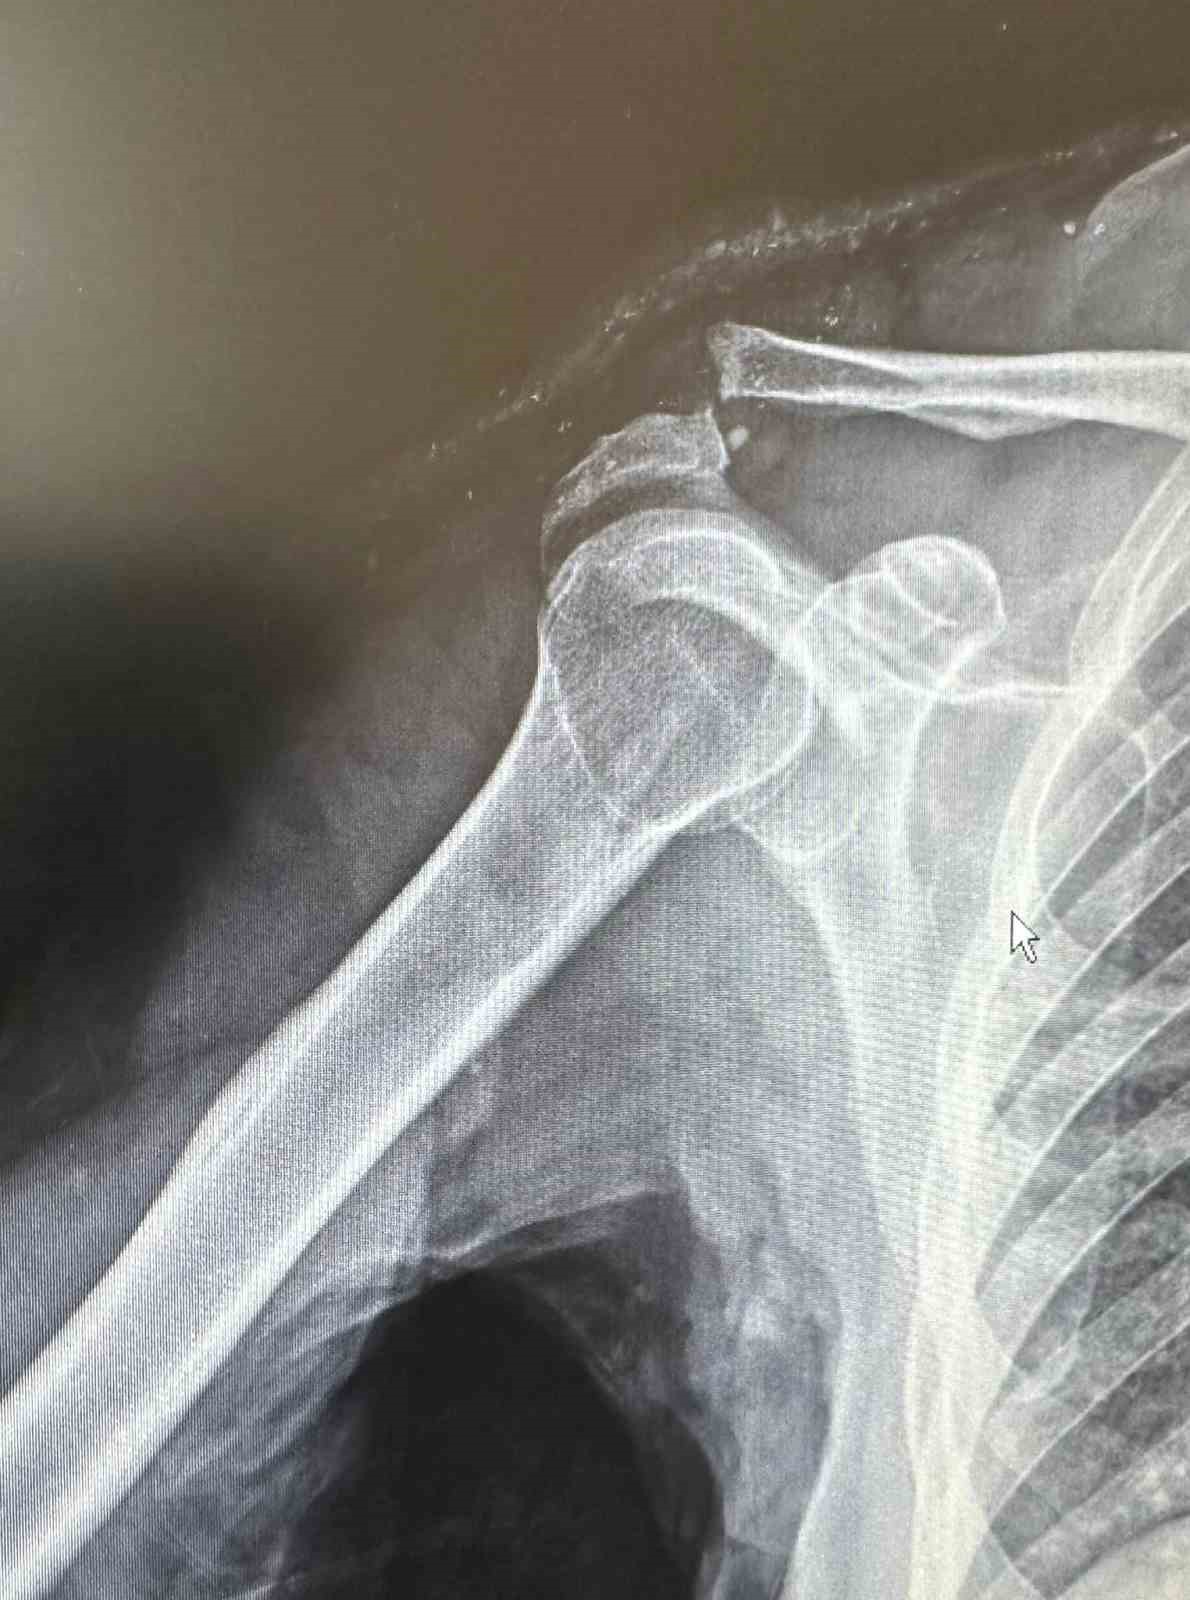

Dr. Başer, hastanın 64 yaşında omuz çıkığı nedeniyle kendilerine başvurduğunu söyledi. Kendisi, arkadaşlarıyla tenis oynarken omuz üzerine düşme sonrası omuzunda bir çıkık geliştiğini belirten Başer, "Normalde bu omuz çıkığını genç hasta grubunda görebiliyoruz. Hastamız ileri yaş olmasına rağmen aktif spor yapan bir hastamız. Bize başvurduğunda omuz eklemi yerinde değildi. Hastanın kemik yapısına tam uyumlu, nadir kullanılan özel bir plak ile başarılı bir ameliyat gerçekleştirdik. Daha sonra biz de ameliyat kararı verdik. Ameliyatında daha çok gençlerde kullanılan nadir, özel şekilli, çengel bir plak kullandık. Daha sonra filmlerini de çekip kontrol ettikten sonra hastamızın ameliyatını başarılı bir şekilde tamamladık. Başarılı ameliyatın ardından hemen fizik tedavi sürecini başlattık. Hastamız bugünden itibaren yavaş yavaş omuz hareketlerini yapabilecek hale geldi. Kol askısından bir an önce kurtulacak ve hastamız en geç 2-3 haftaya kadar eski omuz hareketlerine ağrısız kavuşmasını bekliyoruz" dedi.

Daha önce başvurduğu doktorların ileri yaşı nedeniyle ameliyatın mümkün olmayacağını ve kendiliğinden iyileşmesi gerektiğini söylediklerini belirten Rençber ise, "Benim gibi emekli olan arkadaşlarımla tenis oynarken omuz üstüne düştüm. Düşmem münasebetiyle omuzdaki açılma çok büyüktü. Birkaç doktora gittim ve Bu ameliyatın mümkün olamayacağını, 25 yaşına kadar olan hastaları genelde ameliyat yaptıklarını söylediler. ’Yaşının ileri yaş grubunda olduğunuz için dokunmuyoruz. O kendi kendine iyileşir’ dediler. Sonra da Doktor Mehmet Yavuz Bey’e geldim. Mehmet Yavuz Bey durumu inceledi. Dedi ki, ’yapabilirim.’ Bunda inşallah sıkıntı yaşamasın dedi şimdi başarılı bir ameliyat oldum, çok memnun kaldım. Bayağı ilgilendi. Ameliyat sonrası en ufak bir sancı, bir sıkıntı görmedim ve yaşamadım. Ameliyat sonrası bile omuzum neredeyse eskisi gibi hareket edebiliyorum, kısıtlılığım ilk gün bile ciddi şekilde azaldı" şeklinde konuştu.